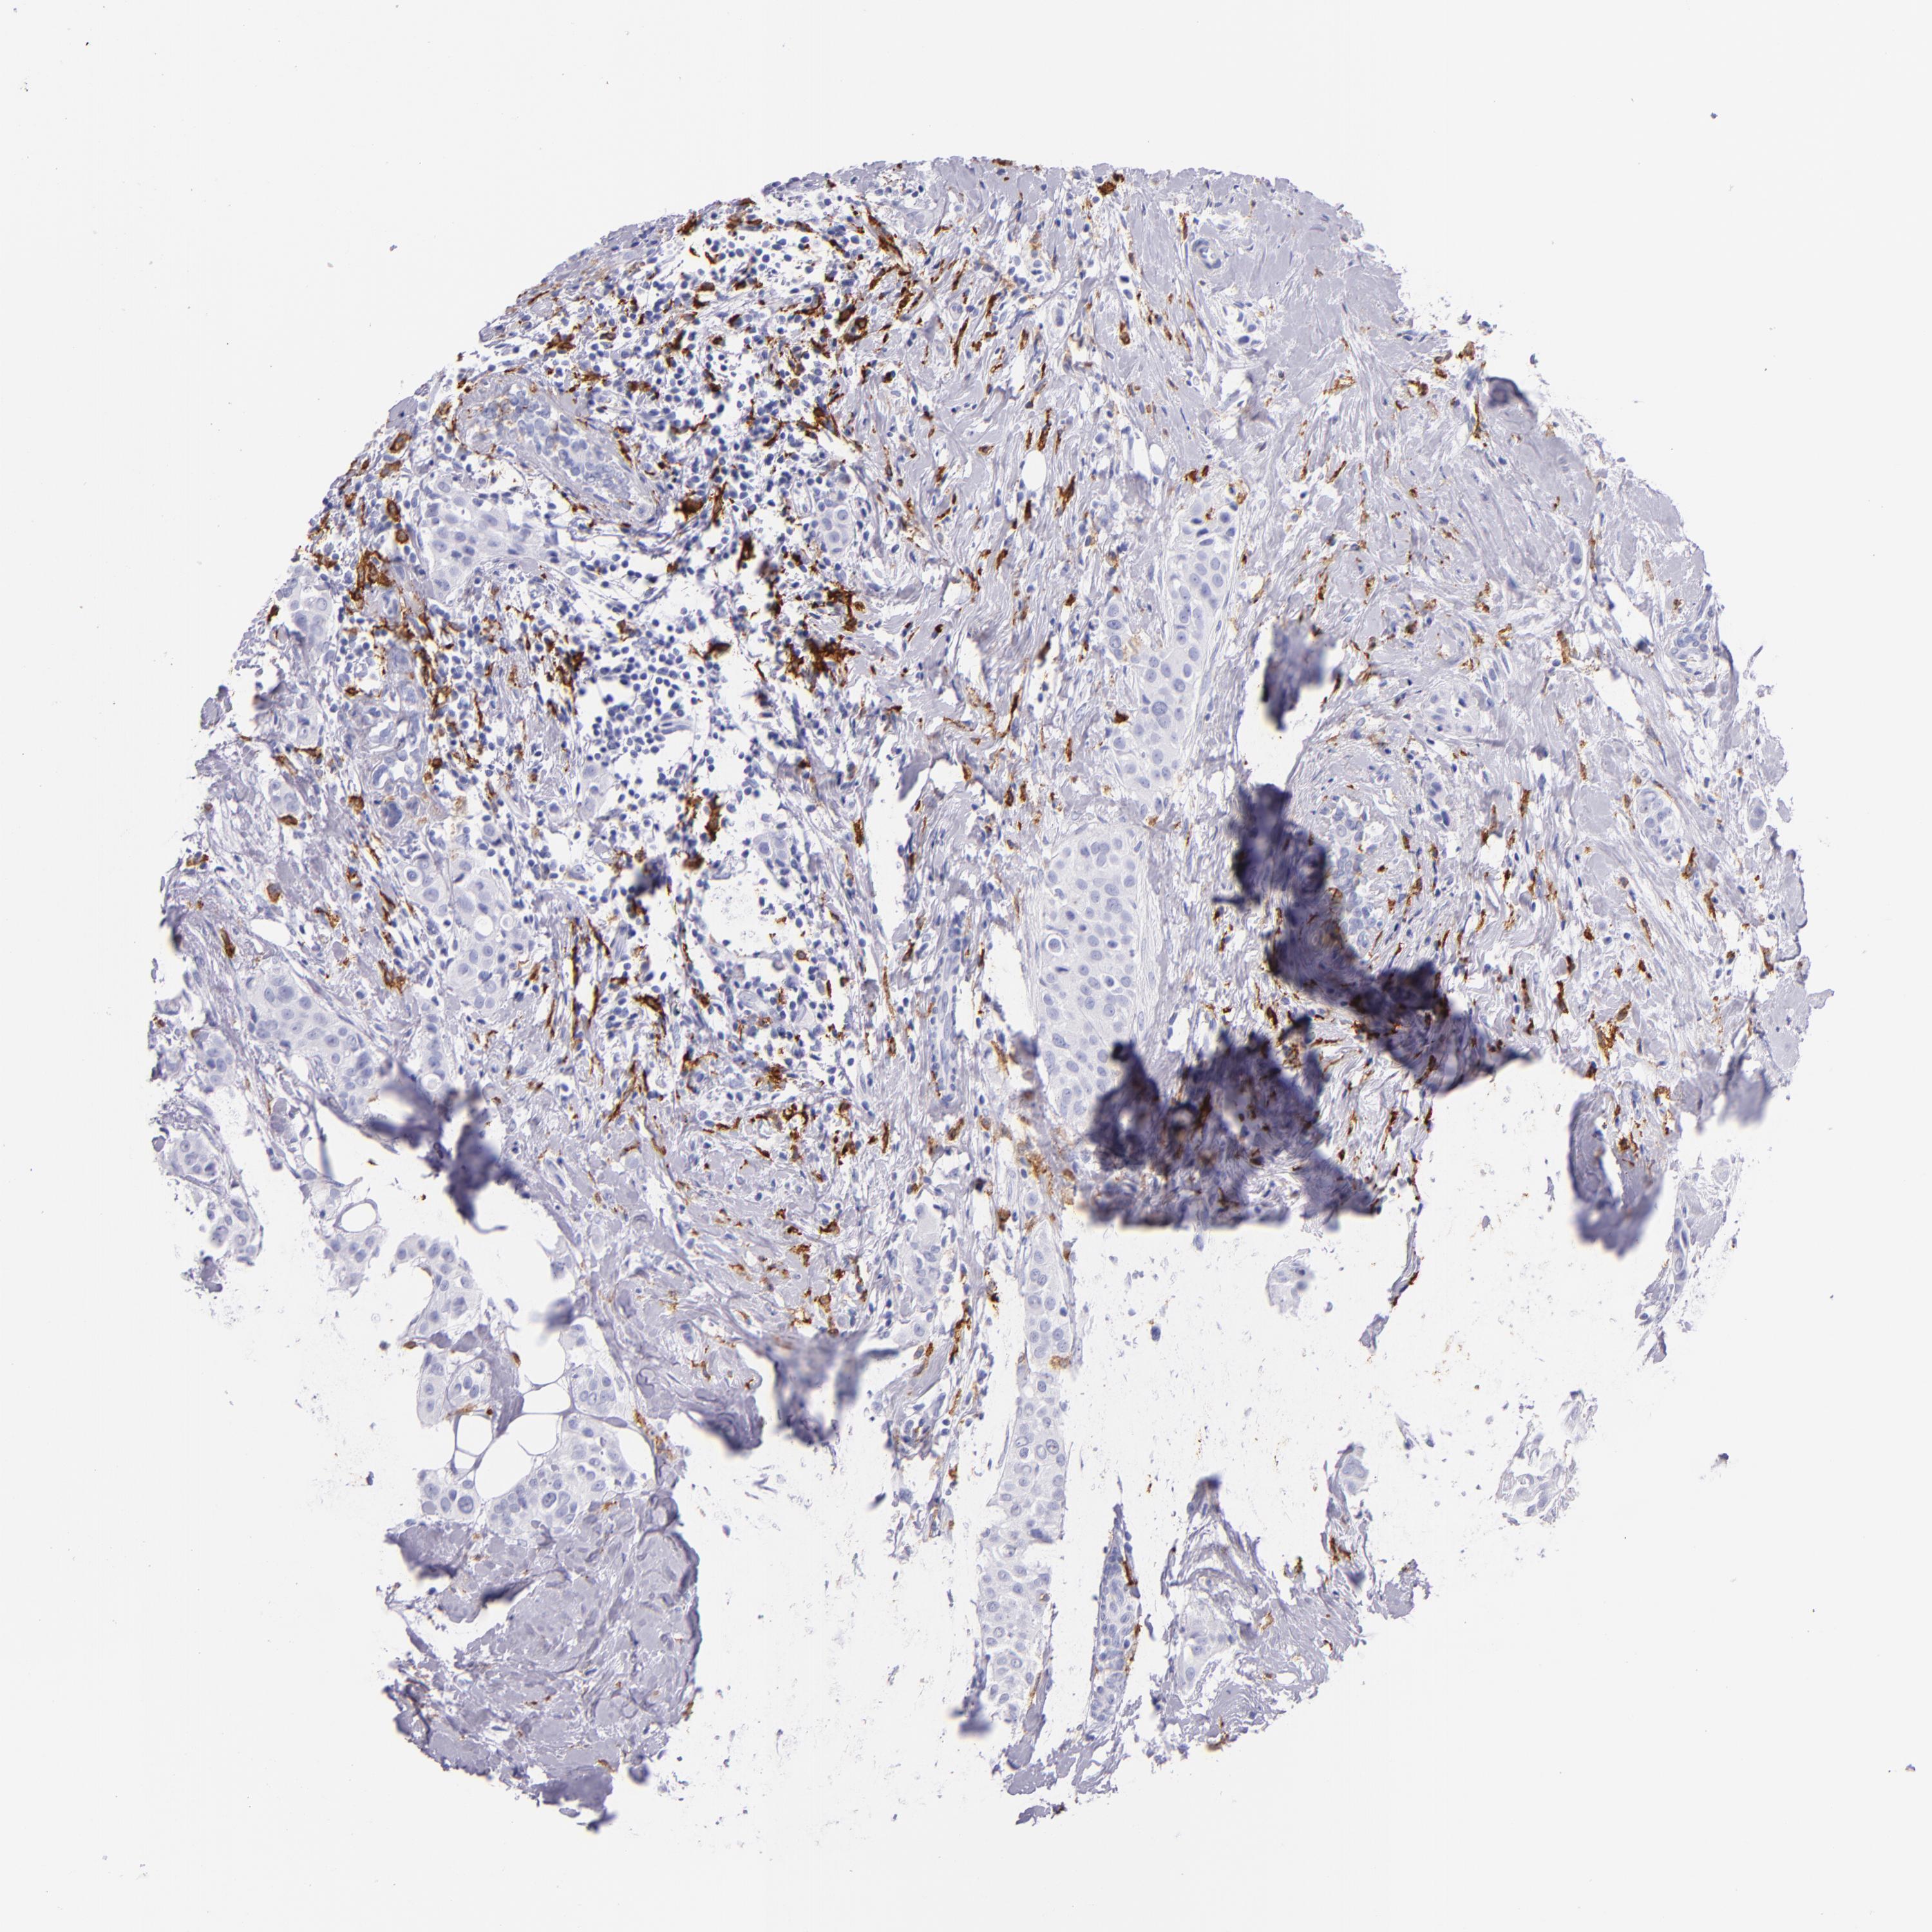

CD163